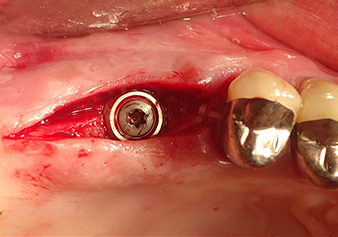

Подготовка ложа имплантата и наращивание

После промежуточного контроля (рис. 4) был проведен еще один этап подготовки (рис. 5). За тем, с помощью гидравлического инструмента Z35P мембрана была поднята в нужное положение (рис. 6 и 7). Далее, следовала дальнейшая пьезохирургическая подготовка ложа для имплантата, завершенная с помощью ротационного бора и лопаточной фрезы до диаметра имплантата 4,8 мм. Перед установкой имплантата под мембрану Шнейдера был введен аугментационный материал (размер частиц около 0,8-1,6 мм) (рис. 8).